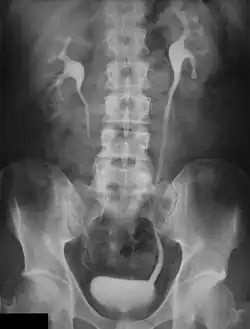

Digital image receptors have been increasingly applied in general radiography since the turn of the century. Early studies indicated its superior image quality relative to film/screen technology in skeletal radiography[1][2]. On this basis, refinements of exposure technique have also occurred[3][4][5][6]. Furthermore, dose comparisons with traditional radiography and various forms of Computed Radiography (CR) with direct and indirect Digital Radiography (DR) have been made[7][8][9]. In addition, the performance of digital image receptors for fluoroscopic applications has also been investigated[10].

Results of these investigations have indicated significant advantages in favour of the digital technology. In general, the change in image receptors has been technically similar to the transition from film-based to digital cameras in photography. However, work practice changes and capital cost are major considerations with the implementation of digital radiography[11].